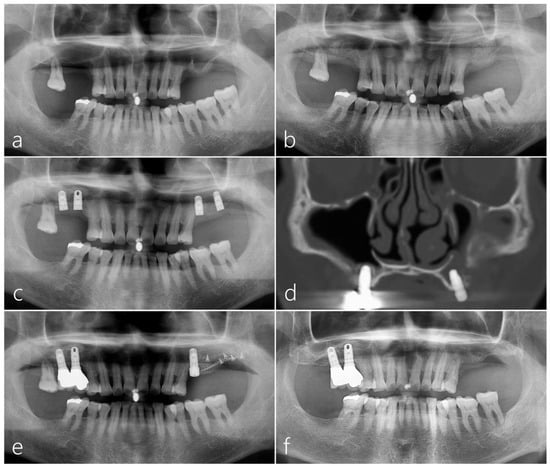

2.1. Case 1

2.2. Case 2